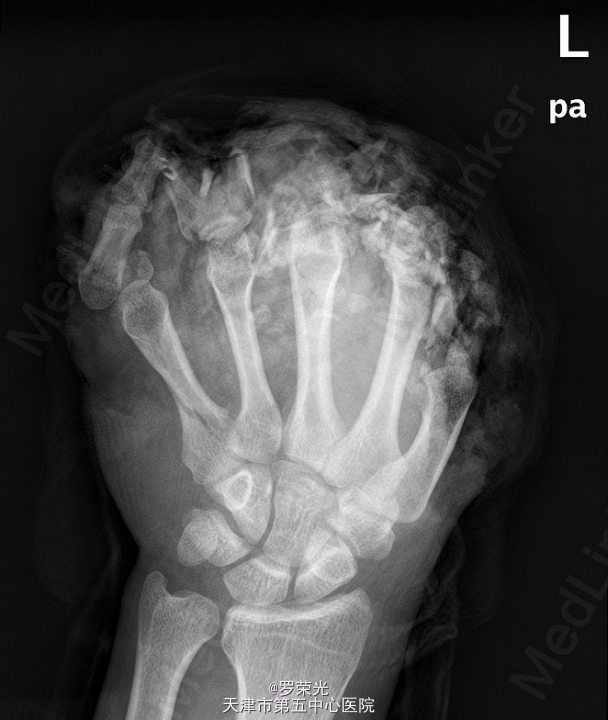

患者,男,30岁,因“左手毁损1月余”入院。

查体:左手远端腹部带蒂皮瓣移植术后,皮肤色泽无殊,未见明显渗出,无红肿疼痛,可触及骨擦感,桡动脉搏动有力,左手活动固定,生理反射存在,未引出病理反射,余肢体末梢血循、感觉、活动正常。本院 X线:左手多发指骨骨折,多发指骨及关节结构显示不清,第2掌骨远端结构欠清,大部指骨缺如或仅剩骨碎片影,周围软组织亦缺如,第5掌骨近段亦见骨折,断端对位尚可;左腕关节在位;附见:左桡骨远端见游离骨片影,考虑骨折。